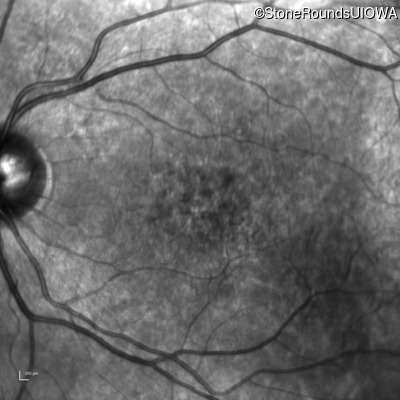

Infrared Fundus Photograph - Right - 20/125

Exemplar